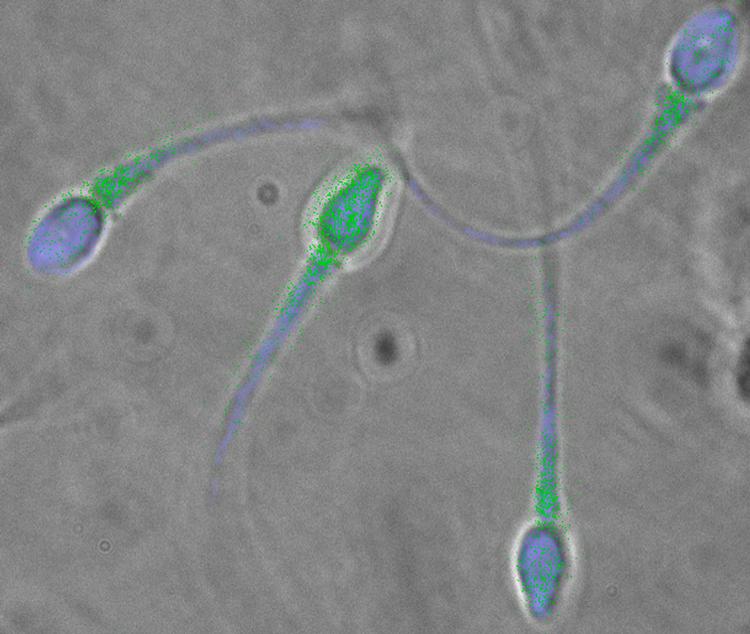

Vi har et kæmpestort sædproblem i den vestlige verden. Heldigvis viser nyere forskning, at man faktisk godt kan gøre noget ved det.  Foto: Ho/Ritzau Scanpix